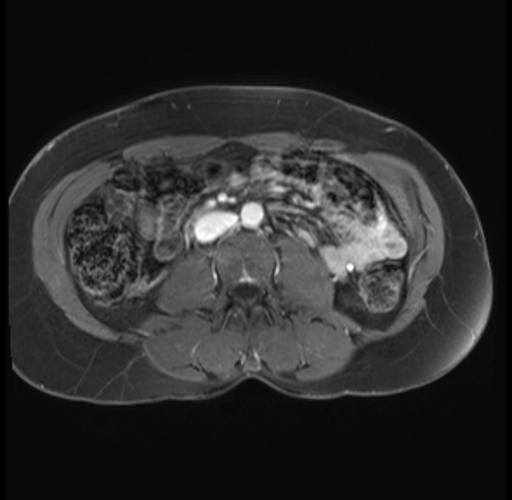

Imaging Analysis

Look through the patient's CT scan to identify any areas of concern for the necessary procedure.

Based on your CT findings, which issue(s) are present and would give reason for "planned slowing down moment(s)" in this case?